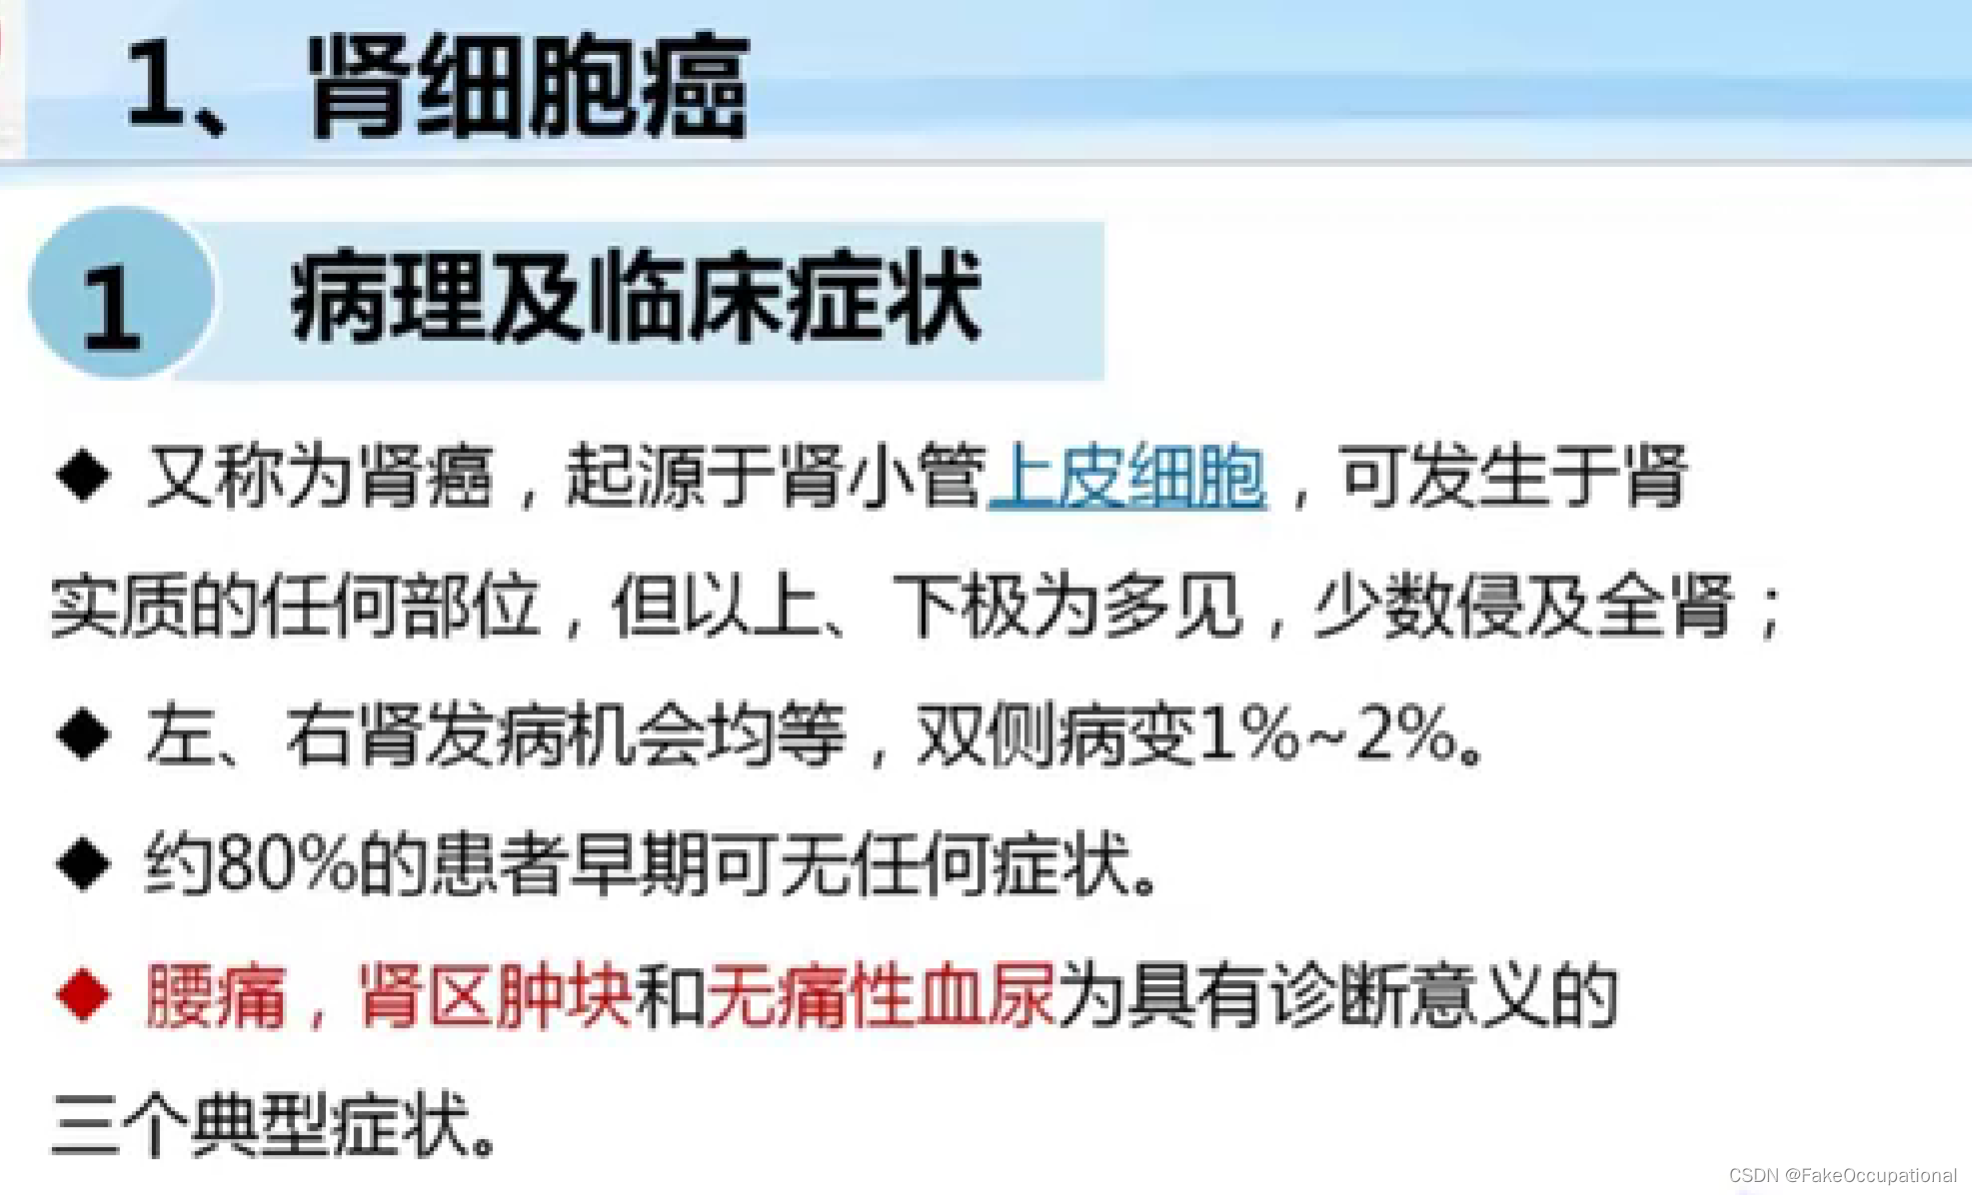

- 掌握肾脏、输尿管膀胱及前列腺疾病的超声诊断要点.1超声表现。熟悉泌尿系统的正常检查技术。了解泌尿系统的超声

- 重点内容:泌尿系的常见疾病

- 难点内容:泌尿系疾病的肿瘤,尤其是恶性肿瘤。